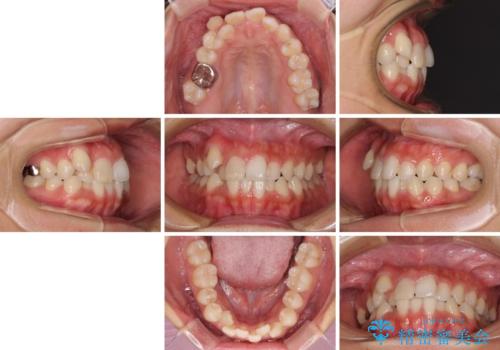

- 八重歯や前歯のデコボコを気にして来院された患者様です。

目立たない装置を希望されたので、上顎が裏側装置のハーフリンガルを選択し、上下左右の小臼歯(計4歯)を抜歯して矯正治療を行うこととしました。

補助装置を併用することで、八重歯を速やかに改善し、治療期間の短縮を図ることとしました。